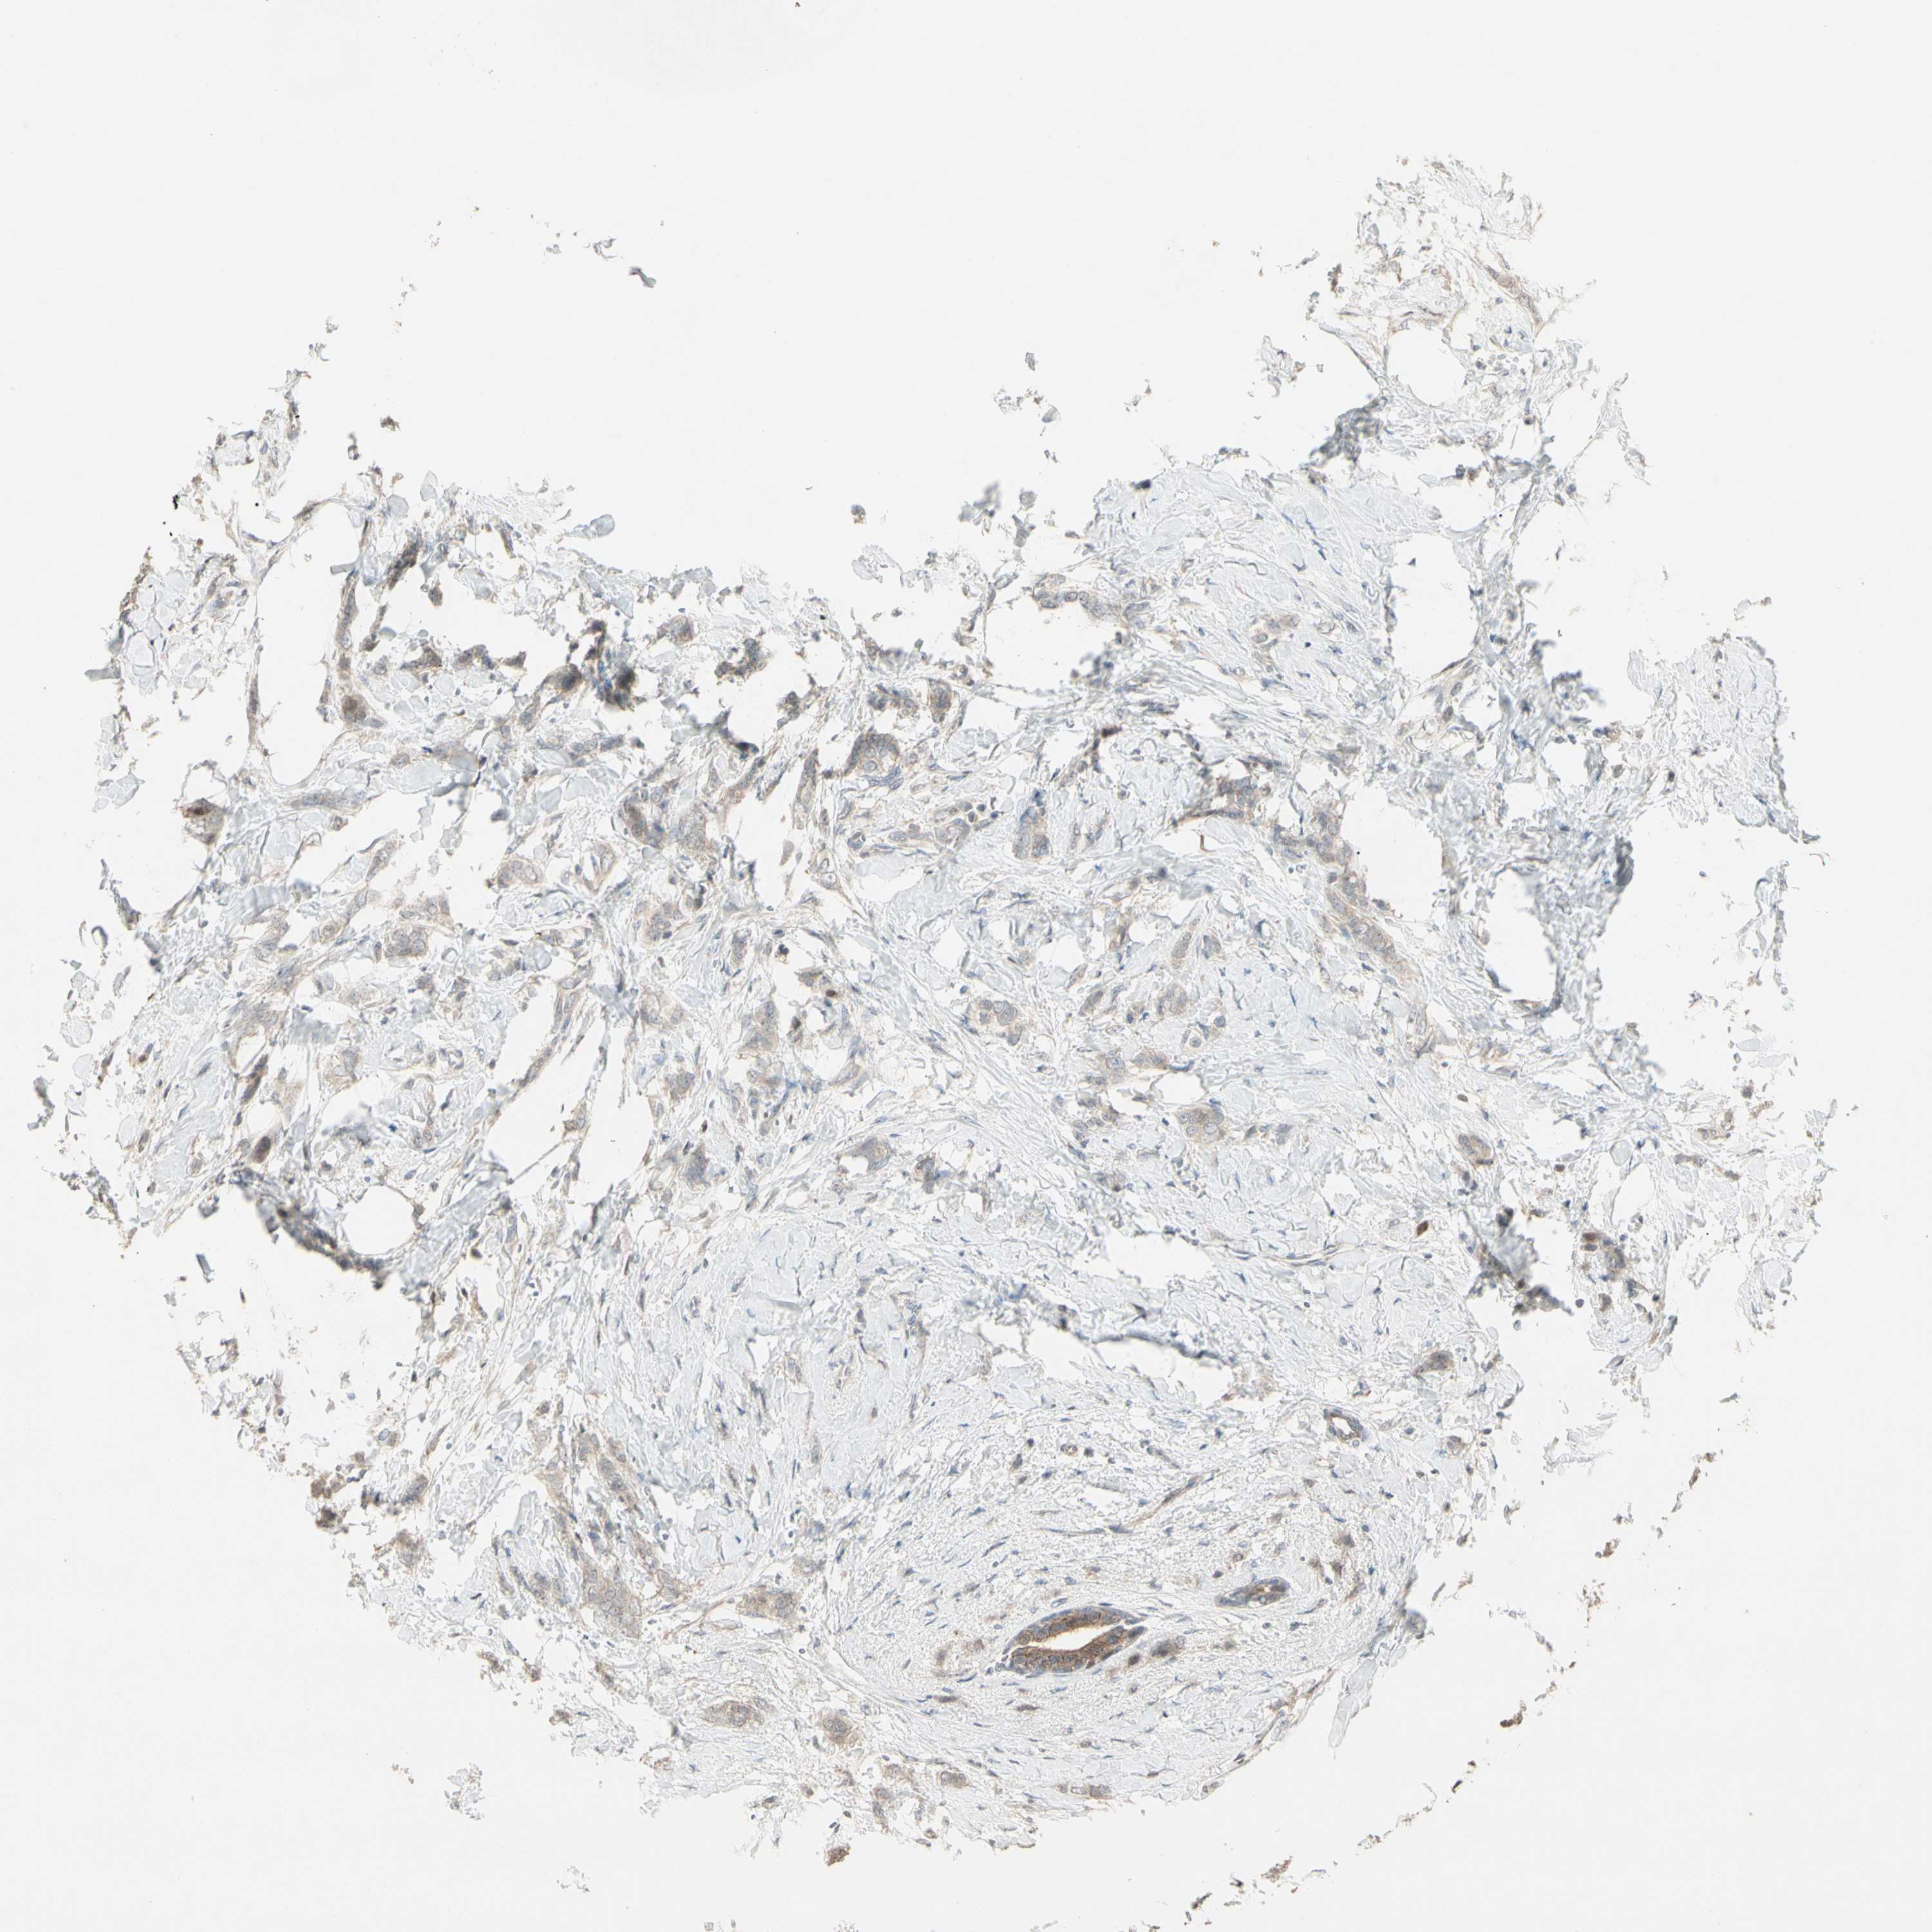

CANCER BREAST CANCER Show tissue menu

BRCA TCGA BRCA VALIDATION PROTEIN EXPRESSION